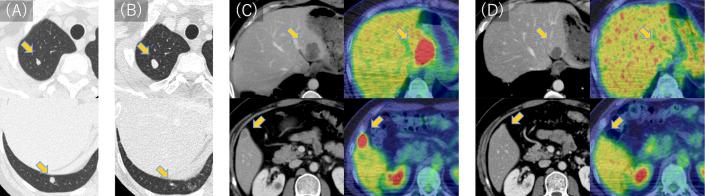

Pleomorphic liposarcoma (PLPS) is a rare and aggressive subtype of liposarcoma with limited treatment options. Despite studies on immune checkpoint inhibitors (ICIs) in sarcomas, there have been few reports involving PLPS. Furthermore, the significance of tumor mutation burden (TMB)-high, a known biomarker for ICIs in various solid tumors, remains unclear in sarcomas. Herein, we report the case of a 41-year-old man with postoperative liver metastasis of microsatellite (MS)-stable/TMB-high PLPS who achieved successful remission with pembrolizumab, an anti-programmed cell death protein 1 inhibitor. Initially, the patient underwent extensive resection for primary PLPS in the distal left thigh. The diagnosis of lung metastases 3 months after prompted five courses of doxorubicin and ifosfamide, resulting in stable disease. Subsequent thoracoscopic pulmonary metastasectomy allowed surgical removal of the lung metastases. However, multiple liver metastases developed 9 months following the primary extensive resection. Cancer genome profiling revealed a mutation in , MS-stable status, and a high TMB of 14.5/Mb. Pembrolizumab was initiated for a total of 35 courses at 10 months postoperatively, significantly reducing liver metastases. These findings suggest the potential of TMB-high as a predictor of ICI response in sarcomas.

多形性脂肪肉瘤(PLPS)是一种罕见且侵袭性强的脂肪肉瘤亚型,治疗选择有限。尽管对肉瘤中免疫检查点抑制剂(ICI)进行了研究,但涉及PLPS的报道很少。此外,肿瘤突变负荷(TMB)高作为各种实体瘤中ICI的已知生物标志物,在肉瘤中的意义仍不明确。在此,我们报告一例41岁男性,患有微卫星(MS)稳定/TMB高的PLPS术后肝转移,使用抗程序性细胞死亡蛋白1抑制剂帕博利珠单抗成功缓解。最初,患者对左大腿远端的原发性PLPS进行了广泛切除。3个月后诊断为肺转移,接受了五个疗程的阿霉素和异环磷酰胺治疗,病情稳定。随后的胸腔镜肺转移瘤切除术成功切除了肺转移灶。然而,在初次广泛切除9个月后出现了多发肝转移。癌症基因组分析显示存在一种突变、MS稳定状态以及14.5/Mb的高TMB。术后10个月开始使用帕博利珠单抗共35个疗程,显著减少了肝转移。这些发现表明TMB高可能作为肉瘤中ICI反应的预测指标。